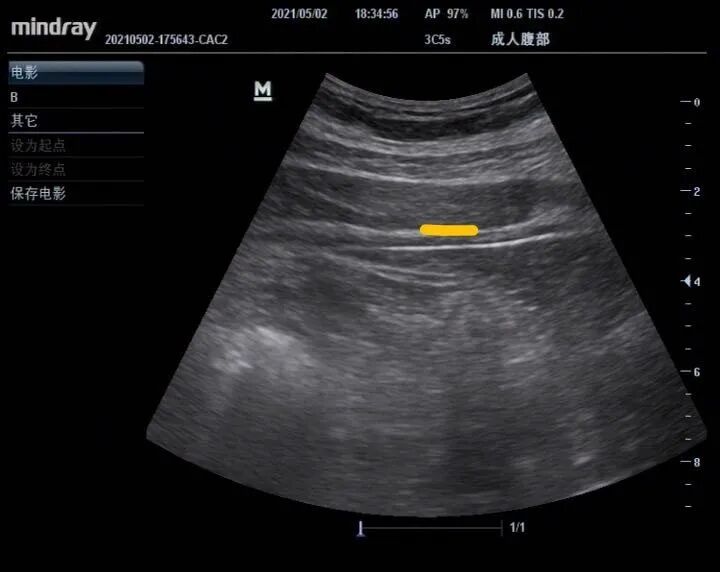

為減輕患者手術(shù)中疼痛感及促使手術(shù)順利進行,近年來TAPB麻醉在腹膜透析置管中的優(yōu)勢逐漸顯現(xiàn)。我科在臧翠平主任的領(lǐng)導(dǎo)下于2018年成立腹膜透析中心,腹膜??漆t(yī)生2名,腹膜??谱o士2名,其中腹膜透析組長周麗波主治醫(yī)生分別于廣州中山大學(xué)附屬第一醫(yī)院及湘雅附三醫(yī)院進修腹膜透析置管術(shù),并在2020年湘雅附三醫(yī)院進修返院后引進TAPB麻醉應(yīng)用于腹膜透析置管手術(shù)。2020年12月開始在腹膜透析置管手術(shù)中應(yīng)用TAPB麻醉,目前我中心已順利開展在彩超引導(dǎo)下行TAPB麻醉應(yīng)用于腹膜透析置管手術(shù)。患者術(shù)中麻醉效果非常滿意,術(shù)后患者評價手術(shù)中無明顯疼痛感。

我科在臧翠平主任的領(lǐng)導(dǎo)下于2018年成立腹膜透析中心,腹膜??漆t(yī)生2名,腹膜專科護士2名,其中腹膜透析組長周麗波主治醫(yī)生分別于廣州中山大學(xué)附屬第一醫(yī)院及湘雅附三醫(yī)院進修腹膜透析置管術(shù),并在2020年湘雅附三醫(yī)院進修返院后引進TAPB麻醉應(yīng)用于腹膜透析置管手術(shù)。目前我中心已順利開展在彩超引導(dǎo)下行TAPB麻醉應(yīng)用于腹膜透析置管術(shù)。